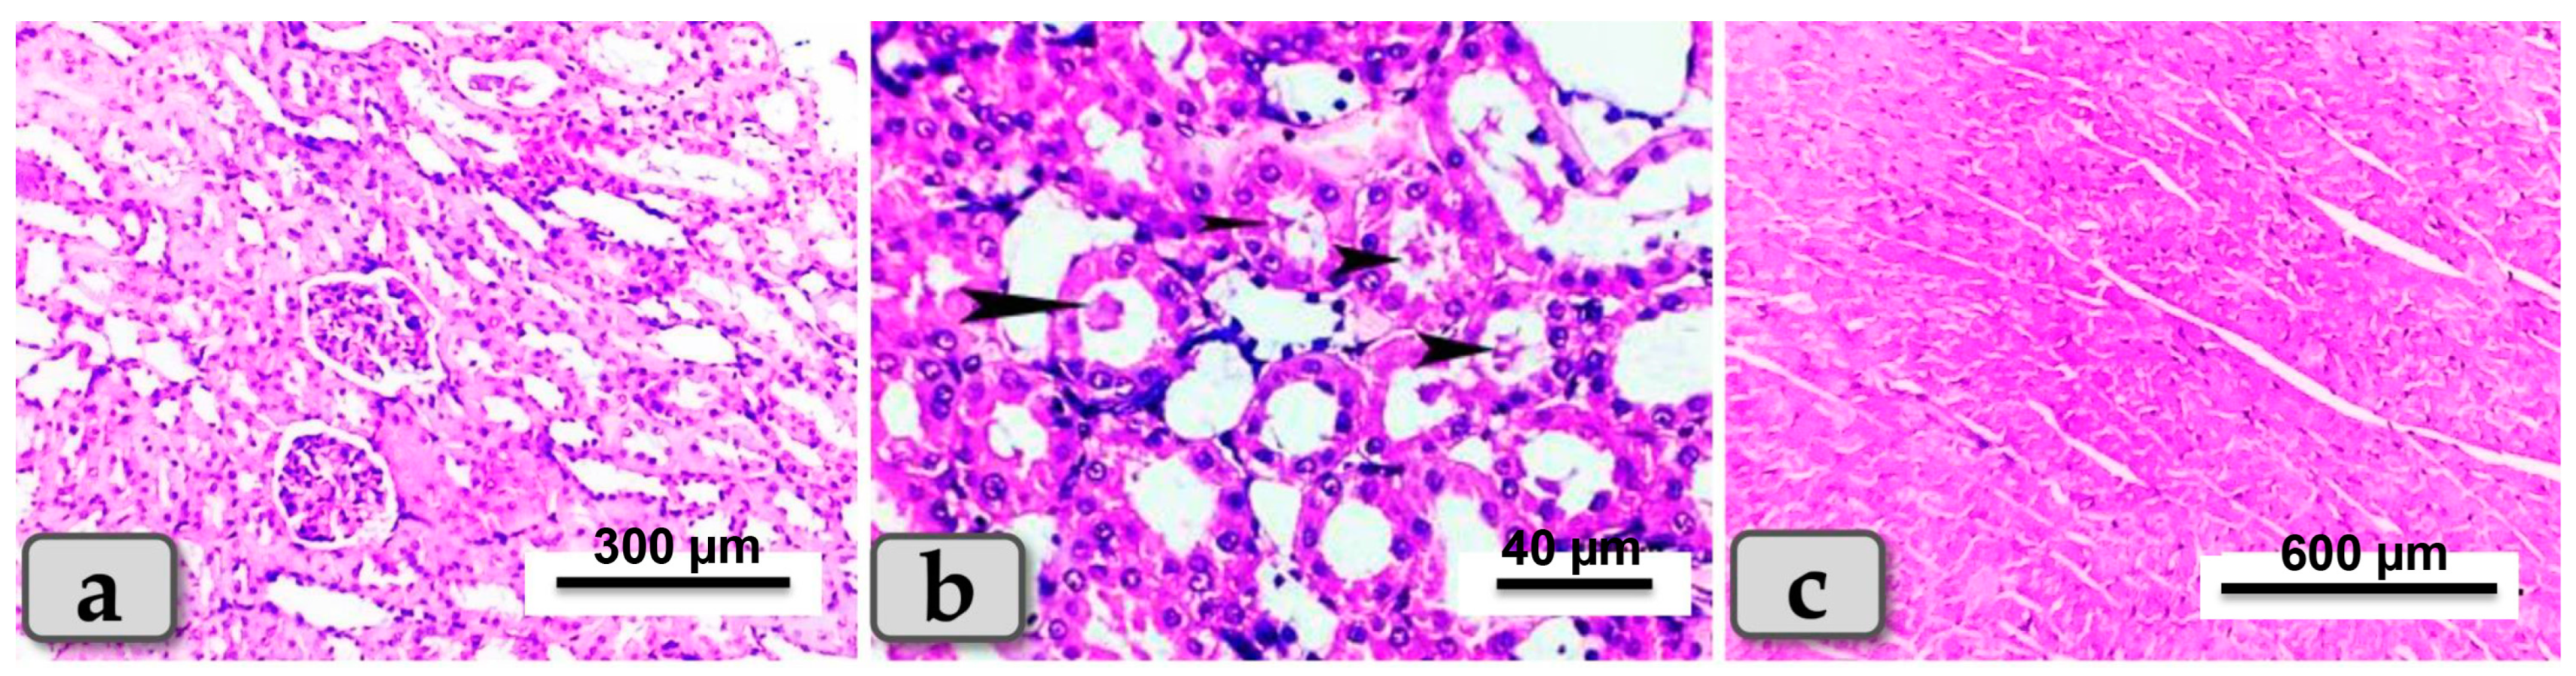

3.5. Histopathological Finding of Renal and Cardiac Tissues due to SeNP and/or BV Administration in STZ-Diabetic Rats

Sacrificed rats of Group 1 (control group) clarified normal, intact renal parenchyma without any pathological changes. The renal parenchyma was organized into two main parts: the outer cortex that houses numerous renal corpuscles surrounded with groups of proximal and distal convoluted tubules; and inner medulla housing numerous medullary rays, bundles of straight tubules, collecting ducts and loops of Henle (Figure 4a). Regarding the heart muscle, this group revealed normal and intact cardiomyocyes with normal orientations and directions, without any pathological abnormalities (Figure 4b).

Figure 4.

Photomicrograph of a rat’s kidney and heart from the control group (Group 1). (a) Showing kidney with normal and intact renal parenchyma, renal cortex and medulla. (b) Showing cardiomyocytes with normal, intact cardiac muscle fibers with normal orientations and directions without any pathological lesions. Stain: All H&E.